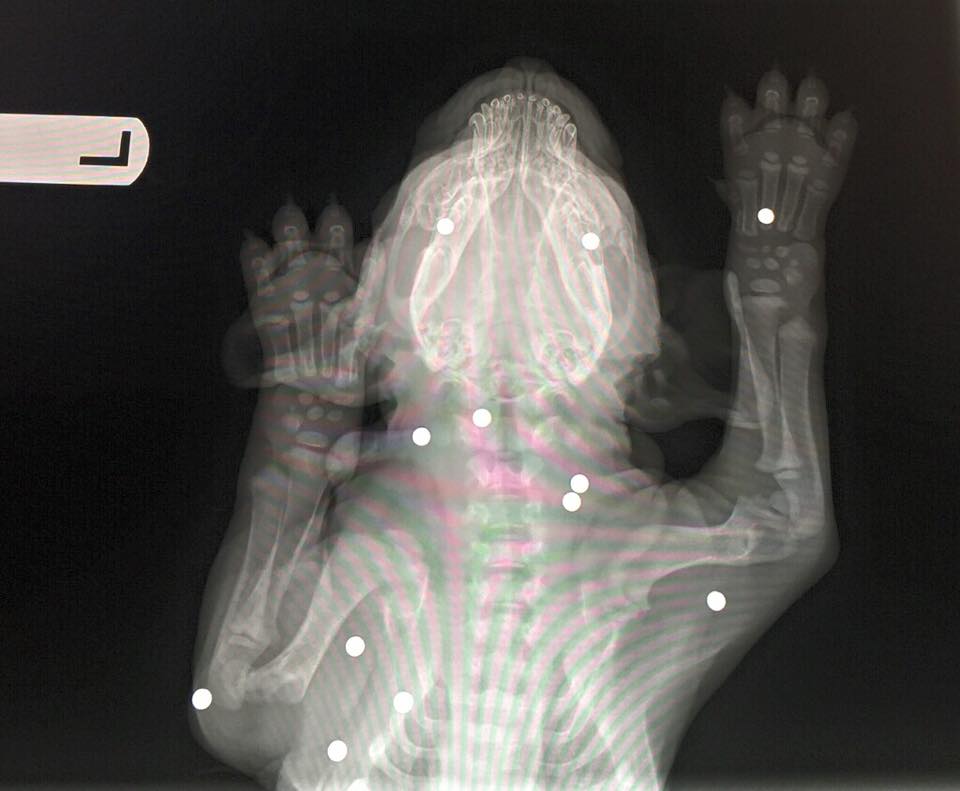

Le week-end dernier, Brody a été retrouvé le corps criblé de 18 balles de plomb dans la ville de Rock Hill en Caroline du Sud (États-Unis). C'est un agent de police qui a porté secours au jeune Labrador de six semaines qui saignait abondamment.

Transporté d'urgence à la clinique pour animauxEbenezer, les vétérinaires découvrent avec stupéfaction la vingtaine deprojectiles logés sous sa peau. Par miracle, aucun n'a atteint sesorganes vitaux ni abîmé sonsquelette.

Le Dr. Jay Hreiz, l'un des médecins du centre, a expliqué à la presse locale:

Pour être tout à fait honnête, je suis très surpris que ce chien aille aussi bien.

Le petit Labrador "a été utilisé pour un sport de tir, ou quelque chose comme ça, par des malades", a expliqué le Dr. Hreiz. Après deux jours d'enquête, la police de Rock Hill aidentifié et arrêté les tortionnaires, deux adolescents de 14 et 17 ans qui s'étaient manifestement amusés à tirer sur le chiot avec des pistolets à air comprimé."C'est difficile de concevoir que quelqu'un puisse être capable de faire du mal à un animal aussi jeune et sans défense", a ajouté le vétérinaire.

Parce qu'il est âgé de quelques semaines à peine, les médecinsontjugé trop risqué d'opérerBrodypour retirer les projectiles.Le Dr. Hreiz a expliqué à The Herald :

Grâce à son jeune âge, il a une très grande capacité de guérison. Brody pourra sans doute mener une vie parfaitement normale avec toutes ces balles dans le corps.